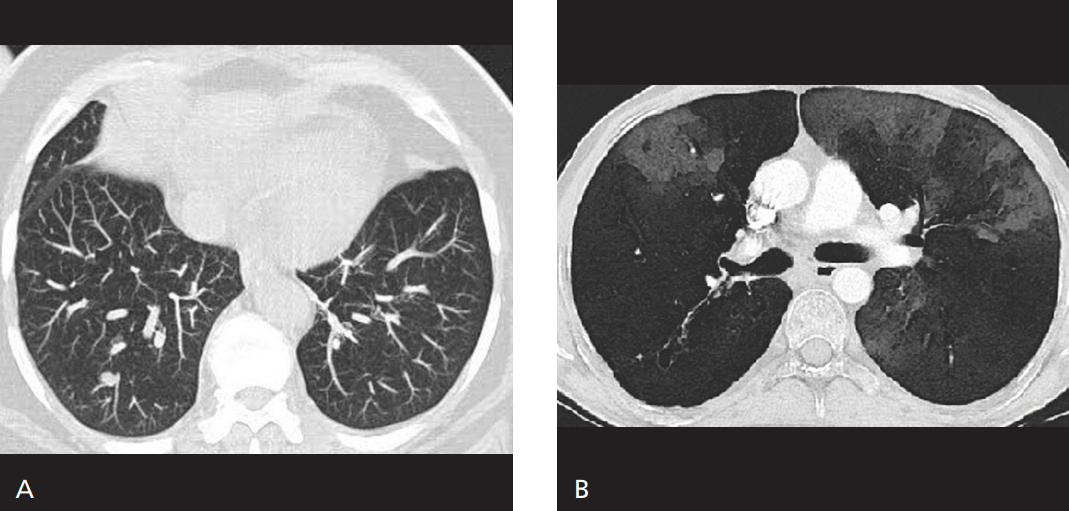

Maximum Intensity Projection (MIP)

Her açıdan en yüksek dansite değerine sahip voksellerin birleştirilerek iki boyutlu görüntüye aktarılması ile oluşturulur. Vaskuler yapıların görüntülenmesinde oldukça sık olarak kullanılan MIP görüntülemenin dezavantajı daha […]